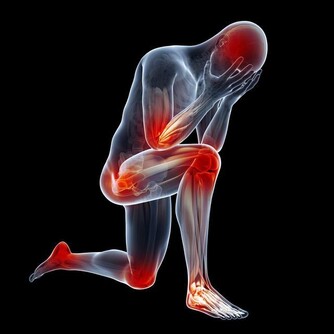

腎陽虛——畏寒怕冷為主要特徵。腎陽虛,會表現出腰部和膝關節酸軟或疼痛,而且發冷,怕冷四肢發涼,下肢尤其嚴重,面色白而沒有光澤或黑而晦暗,神疲乏力,精神萎靡,頭暈目眩;小便清長,夜尿增多,排尿無力,尿後餘瀝不盡,或尿少浮腫;或者肚子脹,容易拉肚子,拉的大便稀而且有不消化的食物,有的人表現為每天黎明時拉肚子;或性慾減退,男子陽痿早洩,遺精滑精;女子宮寒不孕,帶下清稀量多。

腎陰虛——上火為主要特徵。我們將腎陰虛的人稱為“燥熱一族”,他們在腎虛的同時有熱的徵象。腎陰虛體質的人,會出現腰部或膝關節酸軟疼痛,頭暈目眩、耳鳴耳聾、失眠多夢、形體消瘦;兩手心、腳心和心口發熱,身體像潮水一樣一陣一陣的發熱,夜裡睡覺時出汗(盜汗),面紅顴赤,口乾咽燥,大便乾結,小便短少色黃;男子陽強易舉(陰莖容易勃起),遺精早洩;女子月經量少,甚至閉經,或月經淋漓不盡等表現。